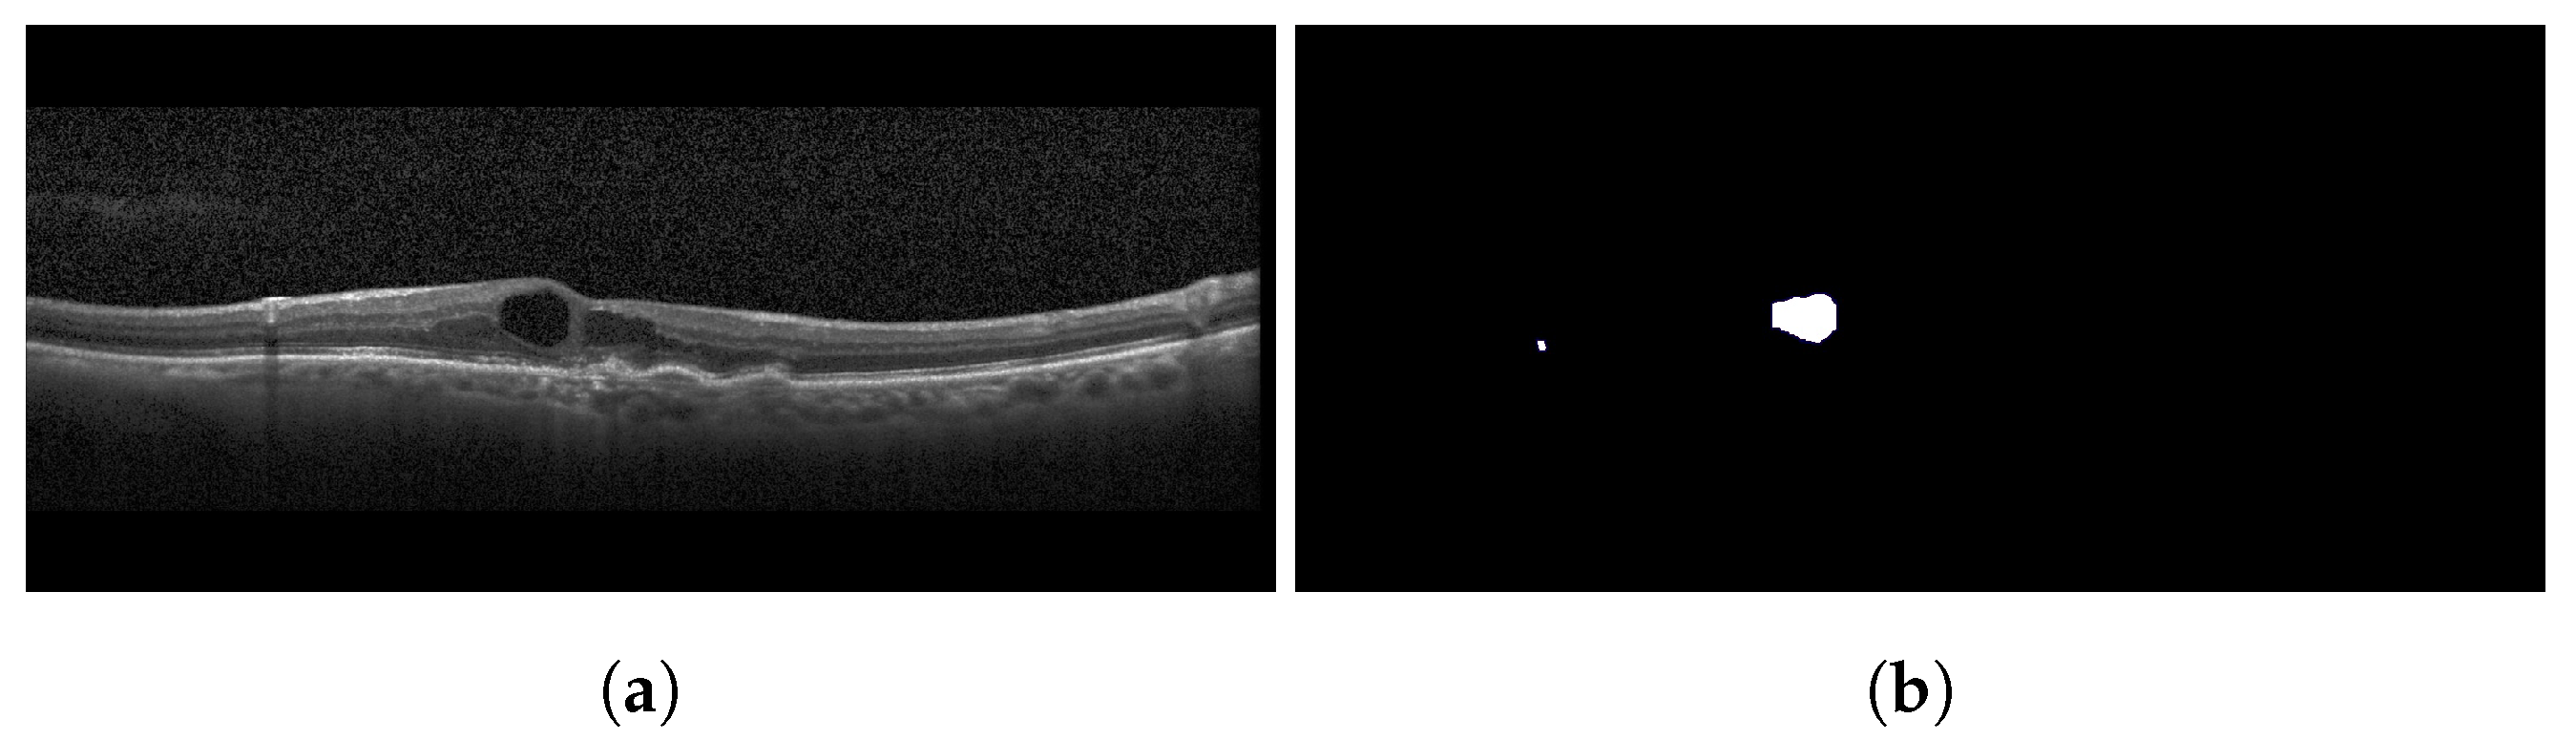

2.3. Cystoid Spaces

3.1.3. Cystoid Space

4.3.3. Cystoids